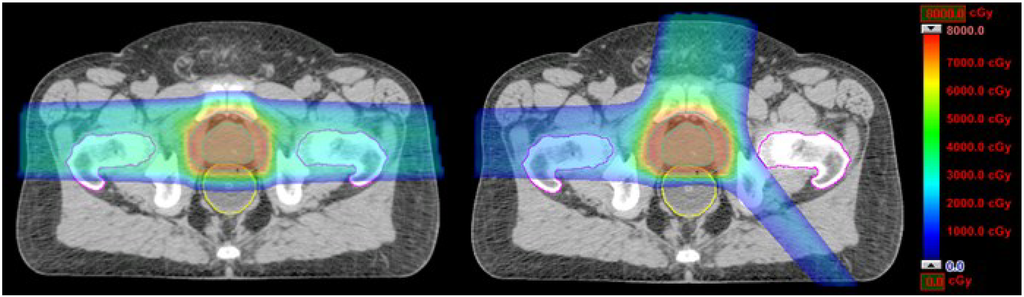

Table 1 shows that at most 5% variation in dose volume data between the optimized and class three-beam-angle plans were observed. This indicates that the advantages of the optimized beam angles could be closely represented by a class three-angle arrangement. The volumes of the rectum receiving doses of 30, 40, 50, 60, and 70 Gy (RBE) and the mean rectum dose in plans with the conventional two beam angles were reduced by 29.6%, 29.7%, 25.7%, 23.1%, 15.9%, and 21.5%, respectively, by plans with the three class beam angles. On the other hand, the dose volumes of the bladder were reduced at −0.4%, 0.5%, 1.9%, 3.8%, 5.3%, 6.7%, and 0.0%, respectively. For illustration, dose distributions of the conventional two-angle plan and the class three-angle plan in an identical transversal plane for patient 1 are shown in Figure 1.

Figure 1.

Dose distribution plots for the conventional two-angle IMPT plans (90°, 270°) and the class three-angle IMPT plans (10°, 140°, 270°) for one prostate cancer patient.